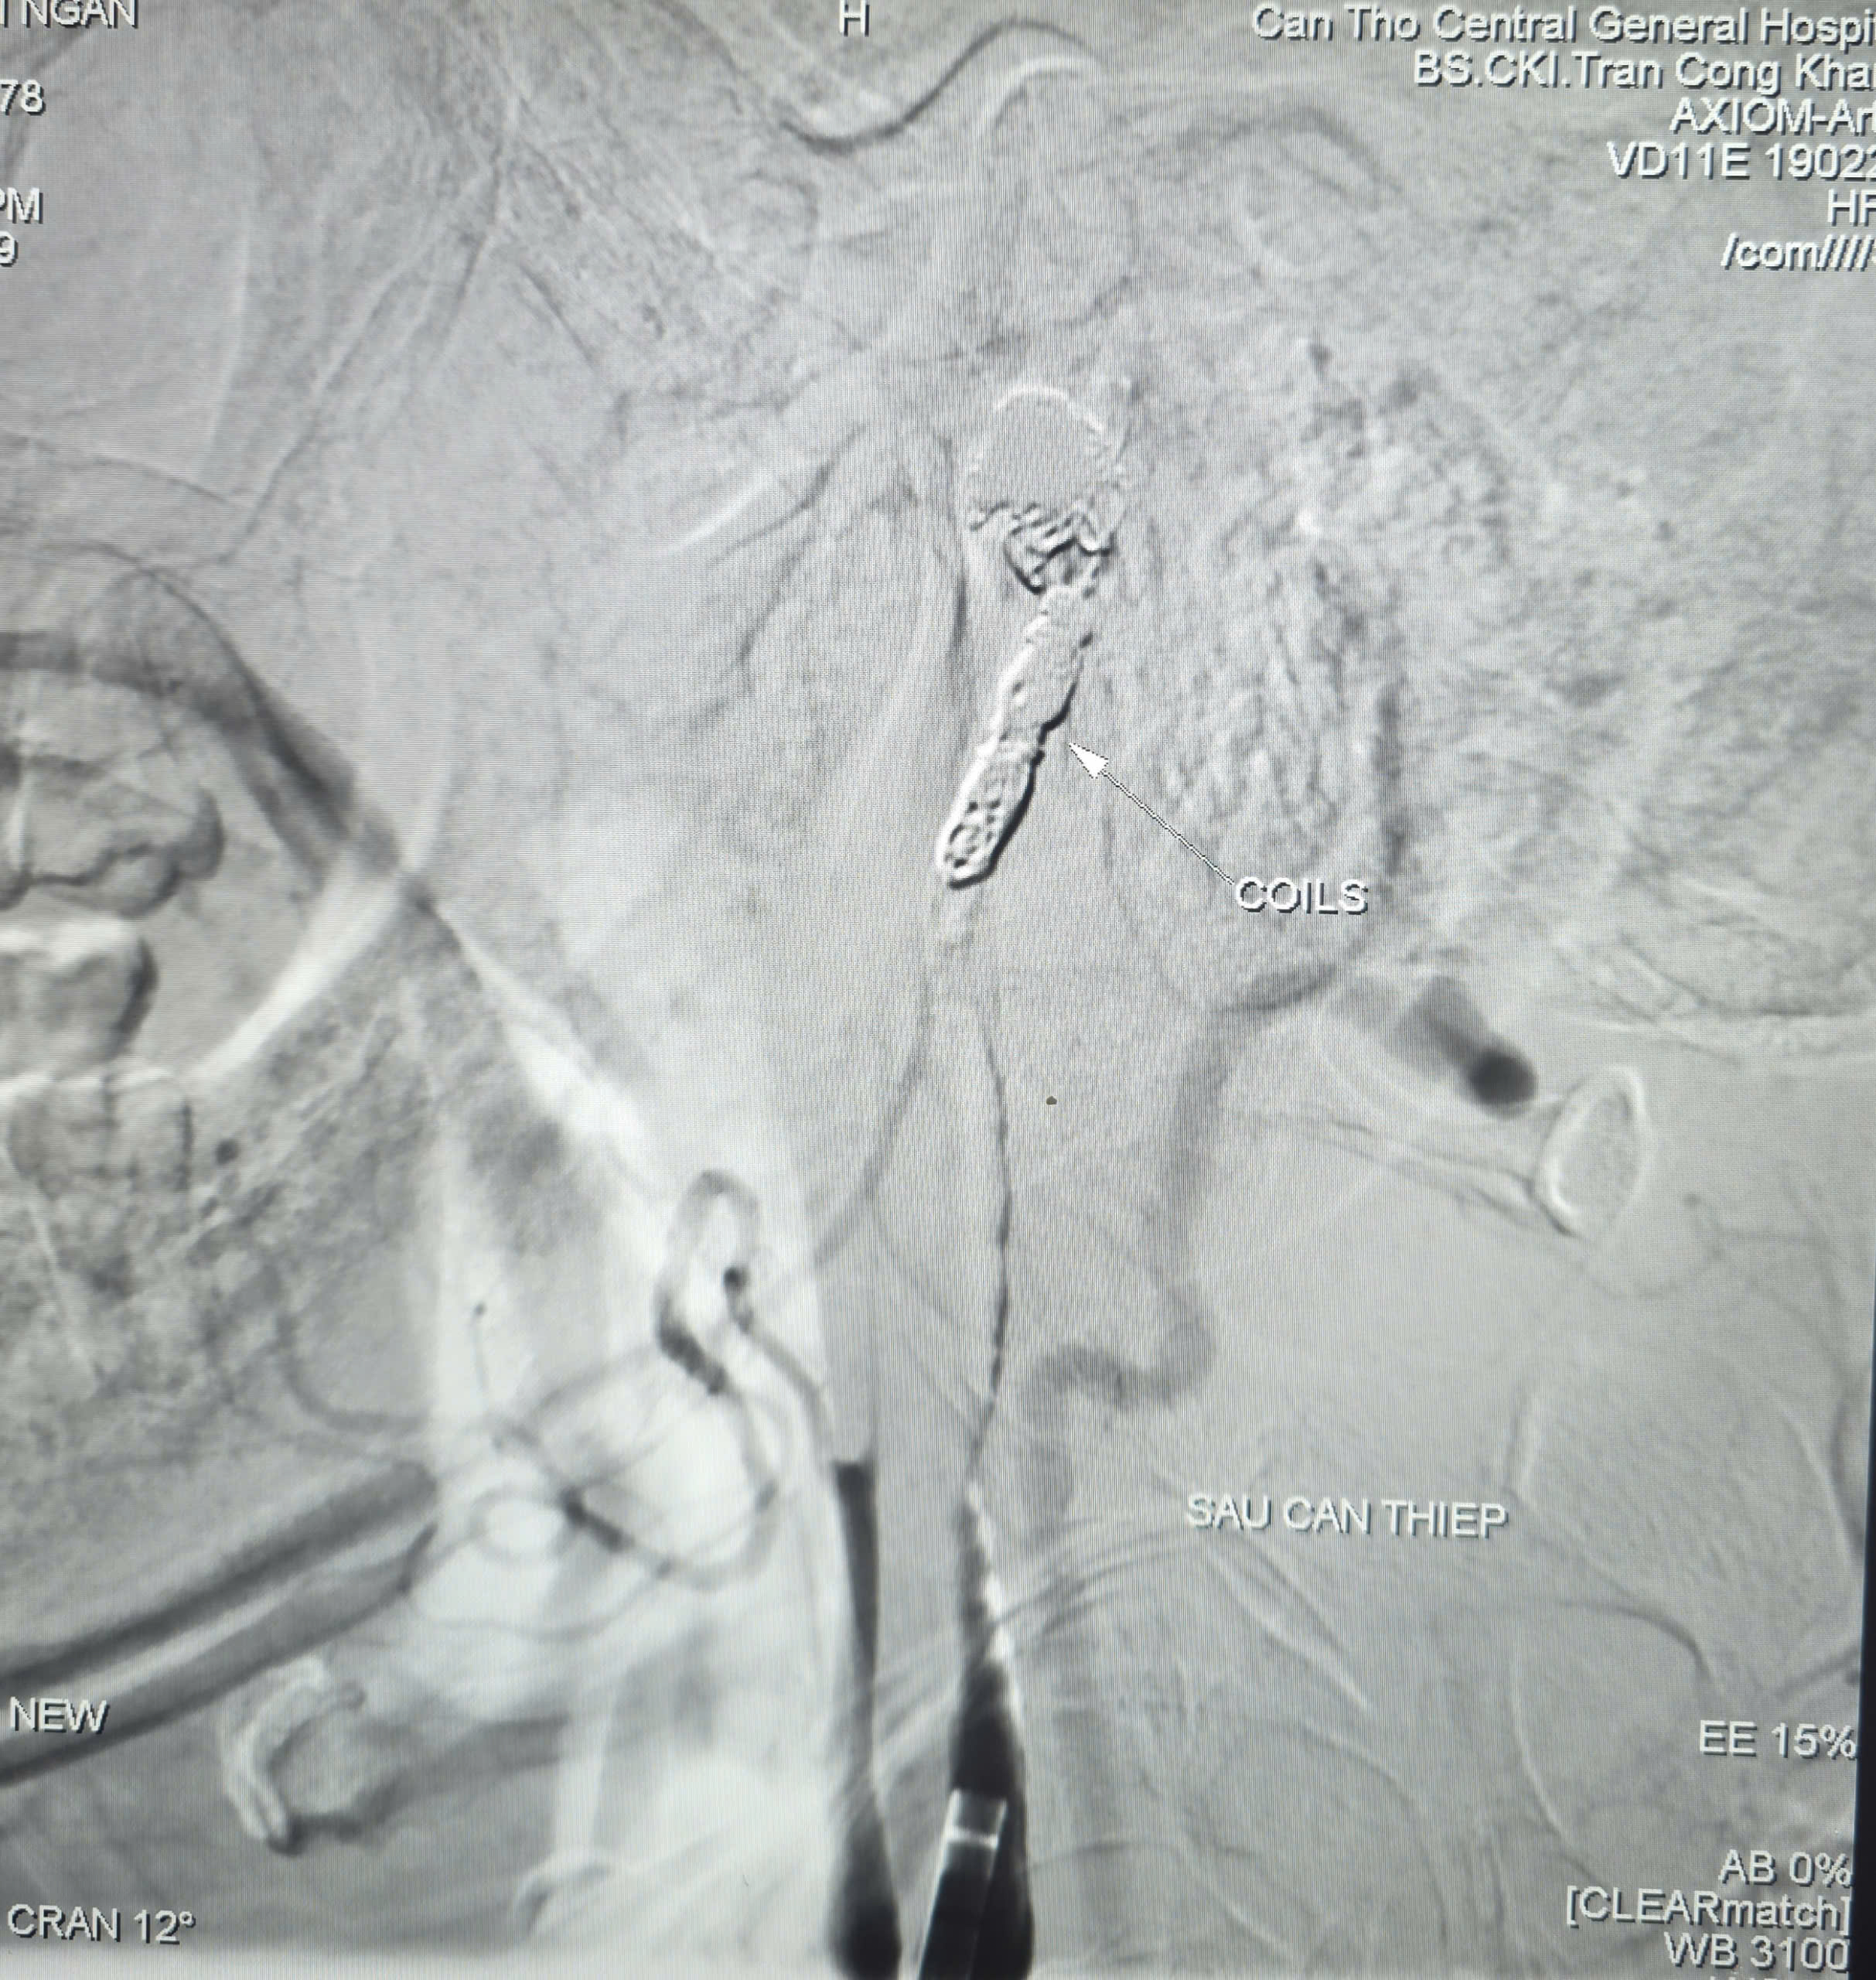

Trước tình huống nguy kịch, nguy cơ mất máu ồ ạt, các bác sĩ quyết định thực hiện chụp và can thiệp cầm máu dưới mạch số hóa xóa nền (DSA). Thủ thuật do BS.CKII. Trần Công Khánh – Phó Trưởng khoa Chẩn đoán hình ảnh cùng ê-kíp thực hiện. Kết quả ghi nhận ổ giả phình động mạch cảnh trong phải đoạn cổ, dưới nền sọ, kích thước 4,2 x 4,8 mm, cổ túi phình rộng và đang chảy máu.

Các bác sĩ đã dùng bóng chẹn dòng chảy kiểm soát lượng máu chảy ra từ túi phình và tiếp tục luồn vi ống thông (ống thông siêu nhỏ) chọn lọc đến vị trí túi phình và tiến hành thả 09 vòng xoắn kim loại (coils) để gây tắc hoàn toàn ổ giả phình và động mạch cảnh trong phải, nhằm kiểm soát triệt để nguồn chảy máu. Chụp kiểm tra từ động mạch cảnh trong trái cho thấy có tuần hoàn bàng hệ nuôi bán cầu não phải qua động mạch thông trước, đảm bảo tưới máu não sau can thiệp. Thời gian hoàn tất can thiệp là 90 phút.

không còn thoát mạch sau can thệp